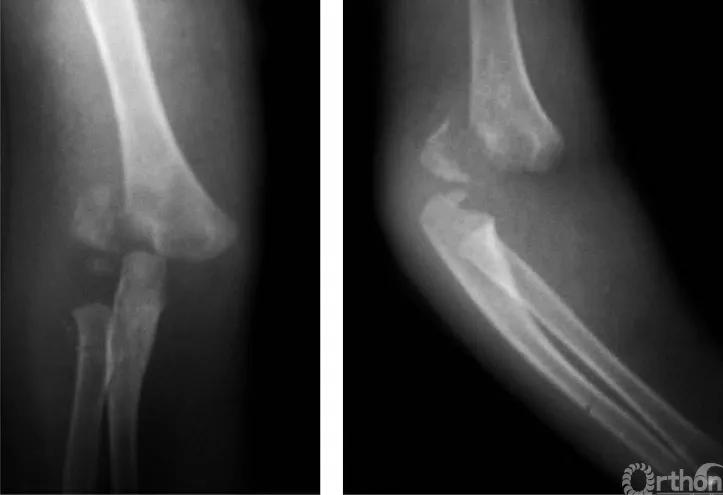

二、尺偏型

例:见肱骨小头及滑车骨骺伴前臂骨一同移向肘之尺侧,并略有旋转(图2)。

图2